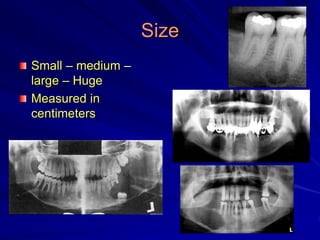

Size

Small – medium –

large – Huge

Measured in

centimeters